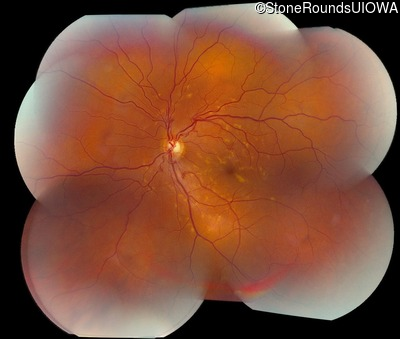

Visit at age: 39 years

Fundus Montage - Right - 20/15

Exemplar